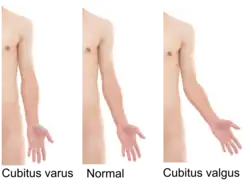

A valgus deformity is a condition in which the bone segment distal to a joint is angled outward, that is, angled laterally, away from the body's midline.[1] The opposite deformation, where the twist or angulation is directed medially, toward the center of the body, is called varus.

- Elbows: cubitus valgus (from Latin cubitus = elbow) – forearm is angled away from the body.

Valgus is a term for outward angulation of the distal segment of a bone or joint. The opposite condition is called varus, which is a medial deviation of the distal bone. The terms "varus" and "valgus" always refer to the direction in which the distal segment of the joint points. The original Latin definitions for varus and valgus were the opposite of their current usage.[2] For a discussion of the etymology of these words, see the entry under varus. A mnemonic to remember the two deformities is that valgus contains an "L", for Lateral deviation.